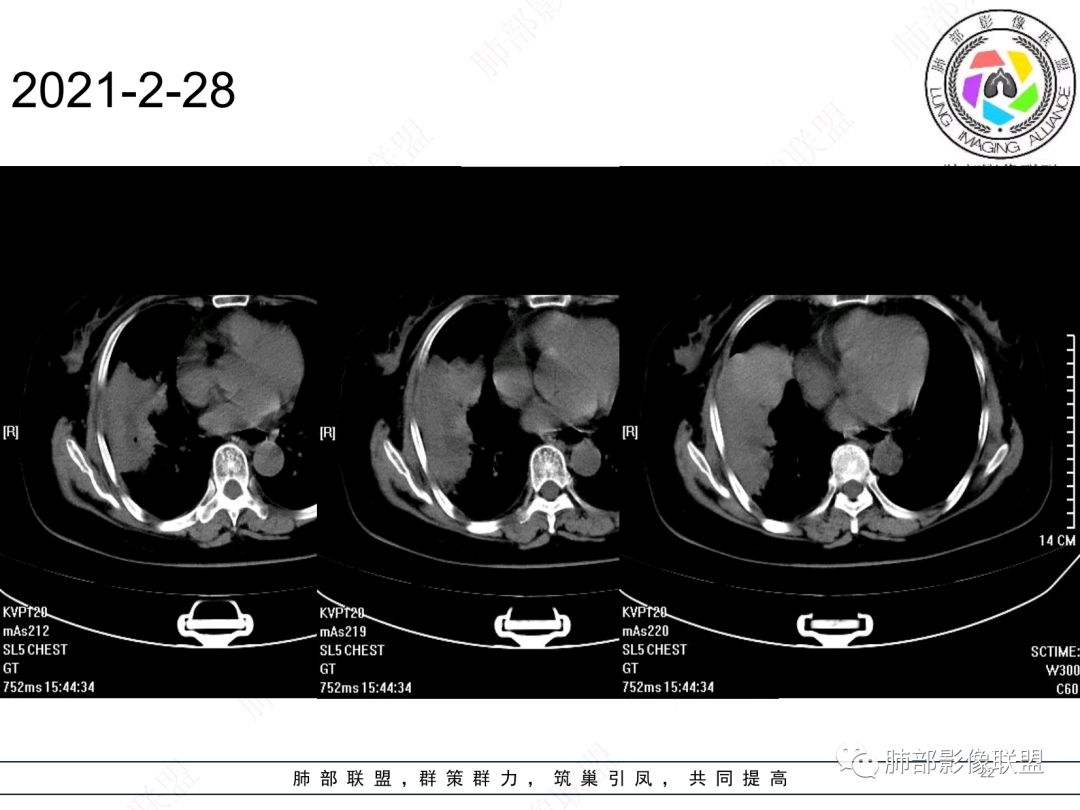

右肺中叶大片实变,内见大片的坏死,中叶外侧段支气管阻塞,相邻胸膜增厚,间隔约四个月后复查,发现低密度坏死内可见气泡影,老年人,反复迁延不愈的病变要考虑恶性,首先考虑腺癌伴感染。鉴别慢性脓肿。

老年女性,慢性病史,炎性指标稍高,肿标正常,右中下肺大片实变,跨叶生长,边界清,收缩力差,膨隆生长为主,支气管杵状截断,均匀强化,其内坏死边界清,可见悬浮气泡,整体观察,病灶膨隆生长为主,邻近肺野无播散灶,形态单一,尽管慢性病史,影像不支持OP和TB,支气管截断呈杵状,肿标正常,均匀强化,虽是高龄患者,诊断恶性肿瘤有点牵强,综和分析,首选炎性病变放线菌感染,其次考虑低度恶性占位炎机母。

这个病灶中叶、下叶都有

坏死腔是连通的

现有的CT,里面存在坏死腔。炎症肯定有,是否同时合并肿瘤的问题?我需要详细的图将内部结构逐步剖析出来,看看能否有新的依据

南边:跨叶、楔形/边缘平直、支气管壁无破坏/连续/局部无膨大、实变区肺动脉走形自然、实性部分均匀、延迟强化、坏死腔内壁光滑/内壁强化环/近端与支气管相通,这些点均支持炎性。所以综合分析:符合炎性。